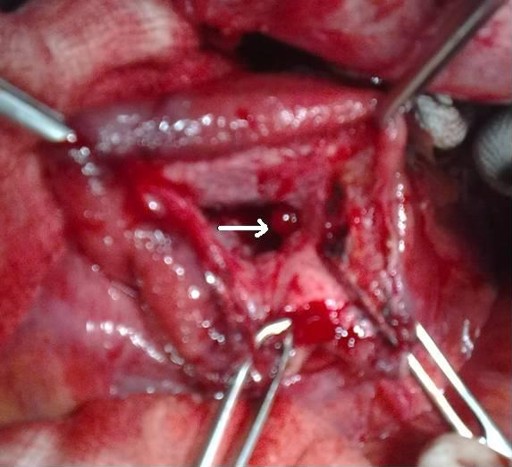

A 26-year-old female presented with a 2-month history of abdominal pain. She was admitted to our institution 7 days after the onset of the pain. She was diagnosed as having gallstone-induced severe acute pancreatitis with a large peripancreatic fluid collection. She was discharged on the 17th day after admission; a cholecystectomy and follow-up for the fluid collection were recommended. Three weeks after discharge, she developed sudden onset of severe abdominal pain with passage of black tarry stool. Hemodynamic stability was maintained. She was re-admitted to our institution. At admission, her pulse was 96 min-1 and her blood pressure was 100/70 mmHg. A lump was palpable in the epigastric region which was non-pulsatile. Hemoglobin was 7.8 g/dL (reference range: 11.5-15.5 g/dL). Upper gastrointestinal endoscopy showed blood in the stomach and duodenum with erosions in the body and antrum of the stomach. She was treated with proton pump inhibitors and blood transfusions. Four days after re-admission, she experienced one episode of hematemesis, and an upper gastrointestinal endoscopy showed blood trickling from the papilla; it was diagnosed as a case of hemosuccus pancreaticus. Contrast-enhanced computed tomography of the abdomen showed a large pseudocyst with extravasation of contrast within the cyst (Figures 2 and 3). The source of bleeding was not identified. Angiography identified a pseudoaneurysm of the gastroduodenal artery. Angioembolization failed due to technical reasons (partial embolization due to a rich collateral supply) and the patient had to undergo emergency surgery. We found that the pseudocyst was full of blood clots and there was a blister-like area in the wall of the cyst (Figure 4). After removal of the clots and slight pressure on the blister-like area, arterial bleeding was seen which was controlled with 4-0-polypropylene sutures. The pseudocyst was drained into the stomach. The patient had an uneventful postoperative course and was well at a 7-month follow-up.

Figure 4. Operative photograph showing blister-like area within the pseudocyst cavity (white arrow) (Case #2). |